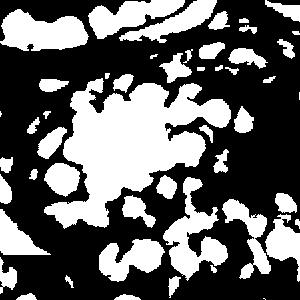

The typical qualitative results of different training strategies from both datasets using 10% points are shown in Fig. 4.

(a) Full

(b) GM

(c) ext-GM

(d) ST-nu

(e) ST-bg

Initial training strategies

In the two initial training strategies, the ext-GM achieves better performance on both datasets. For GM, all the unlabeled nuclei are treated as background, which biases the training and guides the network to predict pixels as background more aggressively. Our extended Gaussian masks force the model to focus on the areas around the labeled points. As a result, the trained model is able to make correct predictions in similar unlabeled regions.

Self-training strategies

In the self-training stage, compared with the results of the first stage (ext-GM), updating the nuclei (ST-nu) decreases the performance. The reason is that the number of false positives in the newly added nuclei is comparable to that of the labeled nuclei, resulting in a negative effect on training. In contrast, our background propagation strategy (ST-bg) keeps the labeled nuclei unchanged and gradually increases the background area (as shown in Fig. 2), which doesn’t introduce false positives during training. Therefore, it can improve both recall and precision, resulting in a much higher F1 score and localization accuracy.

Comparison to fully-supervised case

Compared with the results of full annotation (Full), our method (ST-bg) can achieve comparable performance while using much fewer annotation data. On the LC dataset, the precision, recall and F1 are 98.2%, 100.3%, 99.2% of the fully-supervised results, respectively. And these numbers are 97.8%, 96.1%, 97.0% respectively on the MO dataset. Besides, the localization error is also very close to that using full annotation on both datasets.